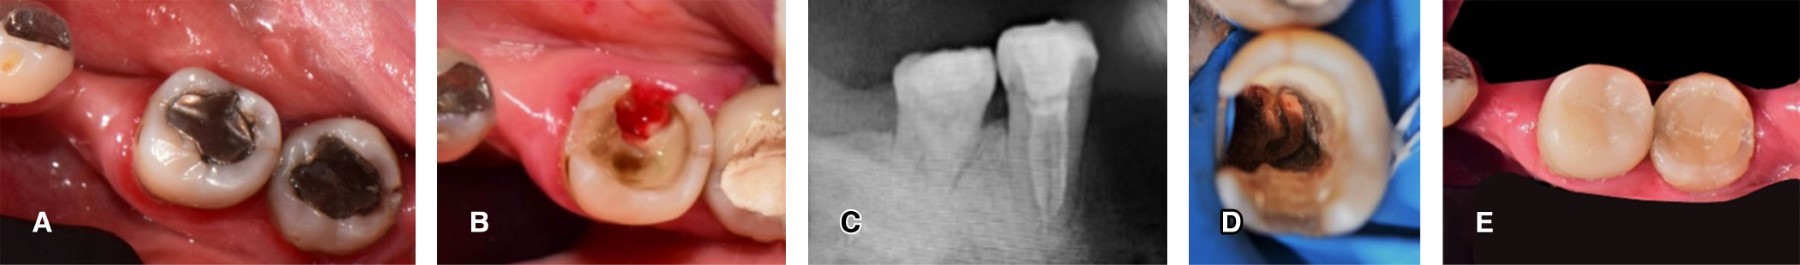

CASO 2

Mujer de 48 años con síndrome de Sjögren secundario acude a consulta para tratamiento integral a la misma clínica de la misma institución. Para rehabilitar los dientes 37 y 36, se eliminan las obturaciones previas y la remoción de lesiones de caries circundante y en cervical del diente 36 (Figura 2A), donde se evidencia gran pérdida de tejido tanto coronal como radicular, con el diagnóstico endodóncico de pulpitis irreversible asintomática, se procede a realizar el tratamiento de conductos, se observa una raíz cónica y una disposición de conductos en C (Figura 2B-C). Terminado el tratamiento de conductos, se determina la colocación de una endocorona ante la imposibilidad de retención de un poste intrarradicular por la disposición de los conductos y el grosor de las paredes radiculares. Se sella el tercio cervical con ionómero de vidrio fotopolimerizable VitrebondTM (3M-ESPE) (Figura 2D).

En la siguiente cita, se conforman las paredes intrapulpares y la zona lingual comprometida con fresa troncocónica 856 (Figura 2B), se eliminó todo tejido remanente frágil y se terminó la preparación coronal y se obtuvo la impresión con PVS Virtual® XD (Ivoclar Vivadent), determinando como material restaurativo final cerómero y se coloca obturación temporal. En la tercera cita, se procede con la prueba y consecuente cementación de la restauración de SR Nexco (Ivoclar Vivadent) con cemento RelyXTM U200 (3M-ESPE), se realizó la remoción de excedentes, el control de oclusión y pulido final (Figura 2E).

Figura 2